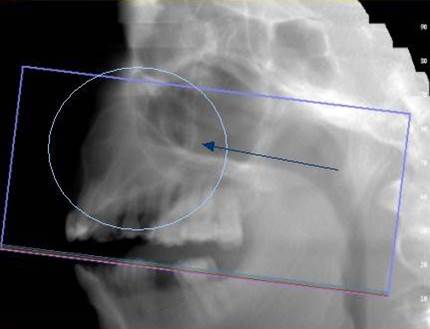

3D DVT - NewTom

Je speciální zubní digitální tříprostorový tomograf (3D), který umožňuje na základě jediného

snímkování vytvořit všechny typy RTG zobrazení, které jsou pro lékaře potřebné. Díky používané technologii tzv. „kuželového paprsku“ a speciálním senzorům je

výrazně zmenšená dávka záření - o více jak 80% proti klasickému CT vyšetření. To je významné zejména u dětí. Pomocí tohoto přístroje je možné zjisti skutečnou situaci v čelistních kostech pacienta tedy množství kosti - můžeme změřit skutečnou šířku i výšku kosti, i kvalitu kosti (hustotu) v místě uvažované implantace. 3D (tříprostorové) zobrazení umožňuje zvýšit prostorovou představu operatéra ještě před vlastní operací a zároveň pacientovi lépe objasnit a ukázat oblast plánovaného zavedení implantátu.

Pacient „neumí číst“ RTG snímky, ale díky 3D zobrazení vidí „svoji skutečnou čelist“

- např. jak je nízká či úzká, vidí průběh nervu nebo velikost čelistní dutiny, což mu umožní i pochopení nutnosti v některých případech provést pomocné zákroky ještě před vlastním zavedením implantátu (viz. kostní štěp, sinus lift, kostní granulát...).

Vyšetření pomocí tohoto přístroje používáme i ve stomatochirurgii (zlomeniny čelistí, zuby moudrosti, cysty, onemocnění čelistního kloubu), ortodoncii (retinované zuby, nadpočetné zuby), parodontologii atd.